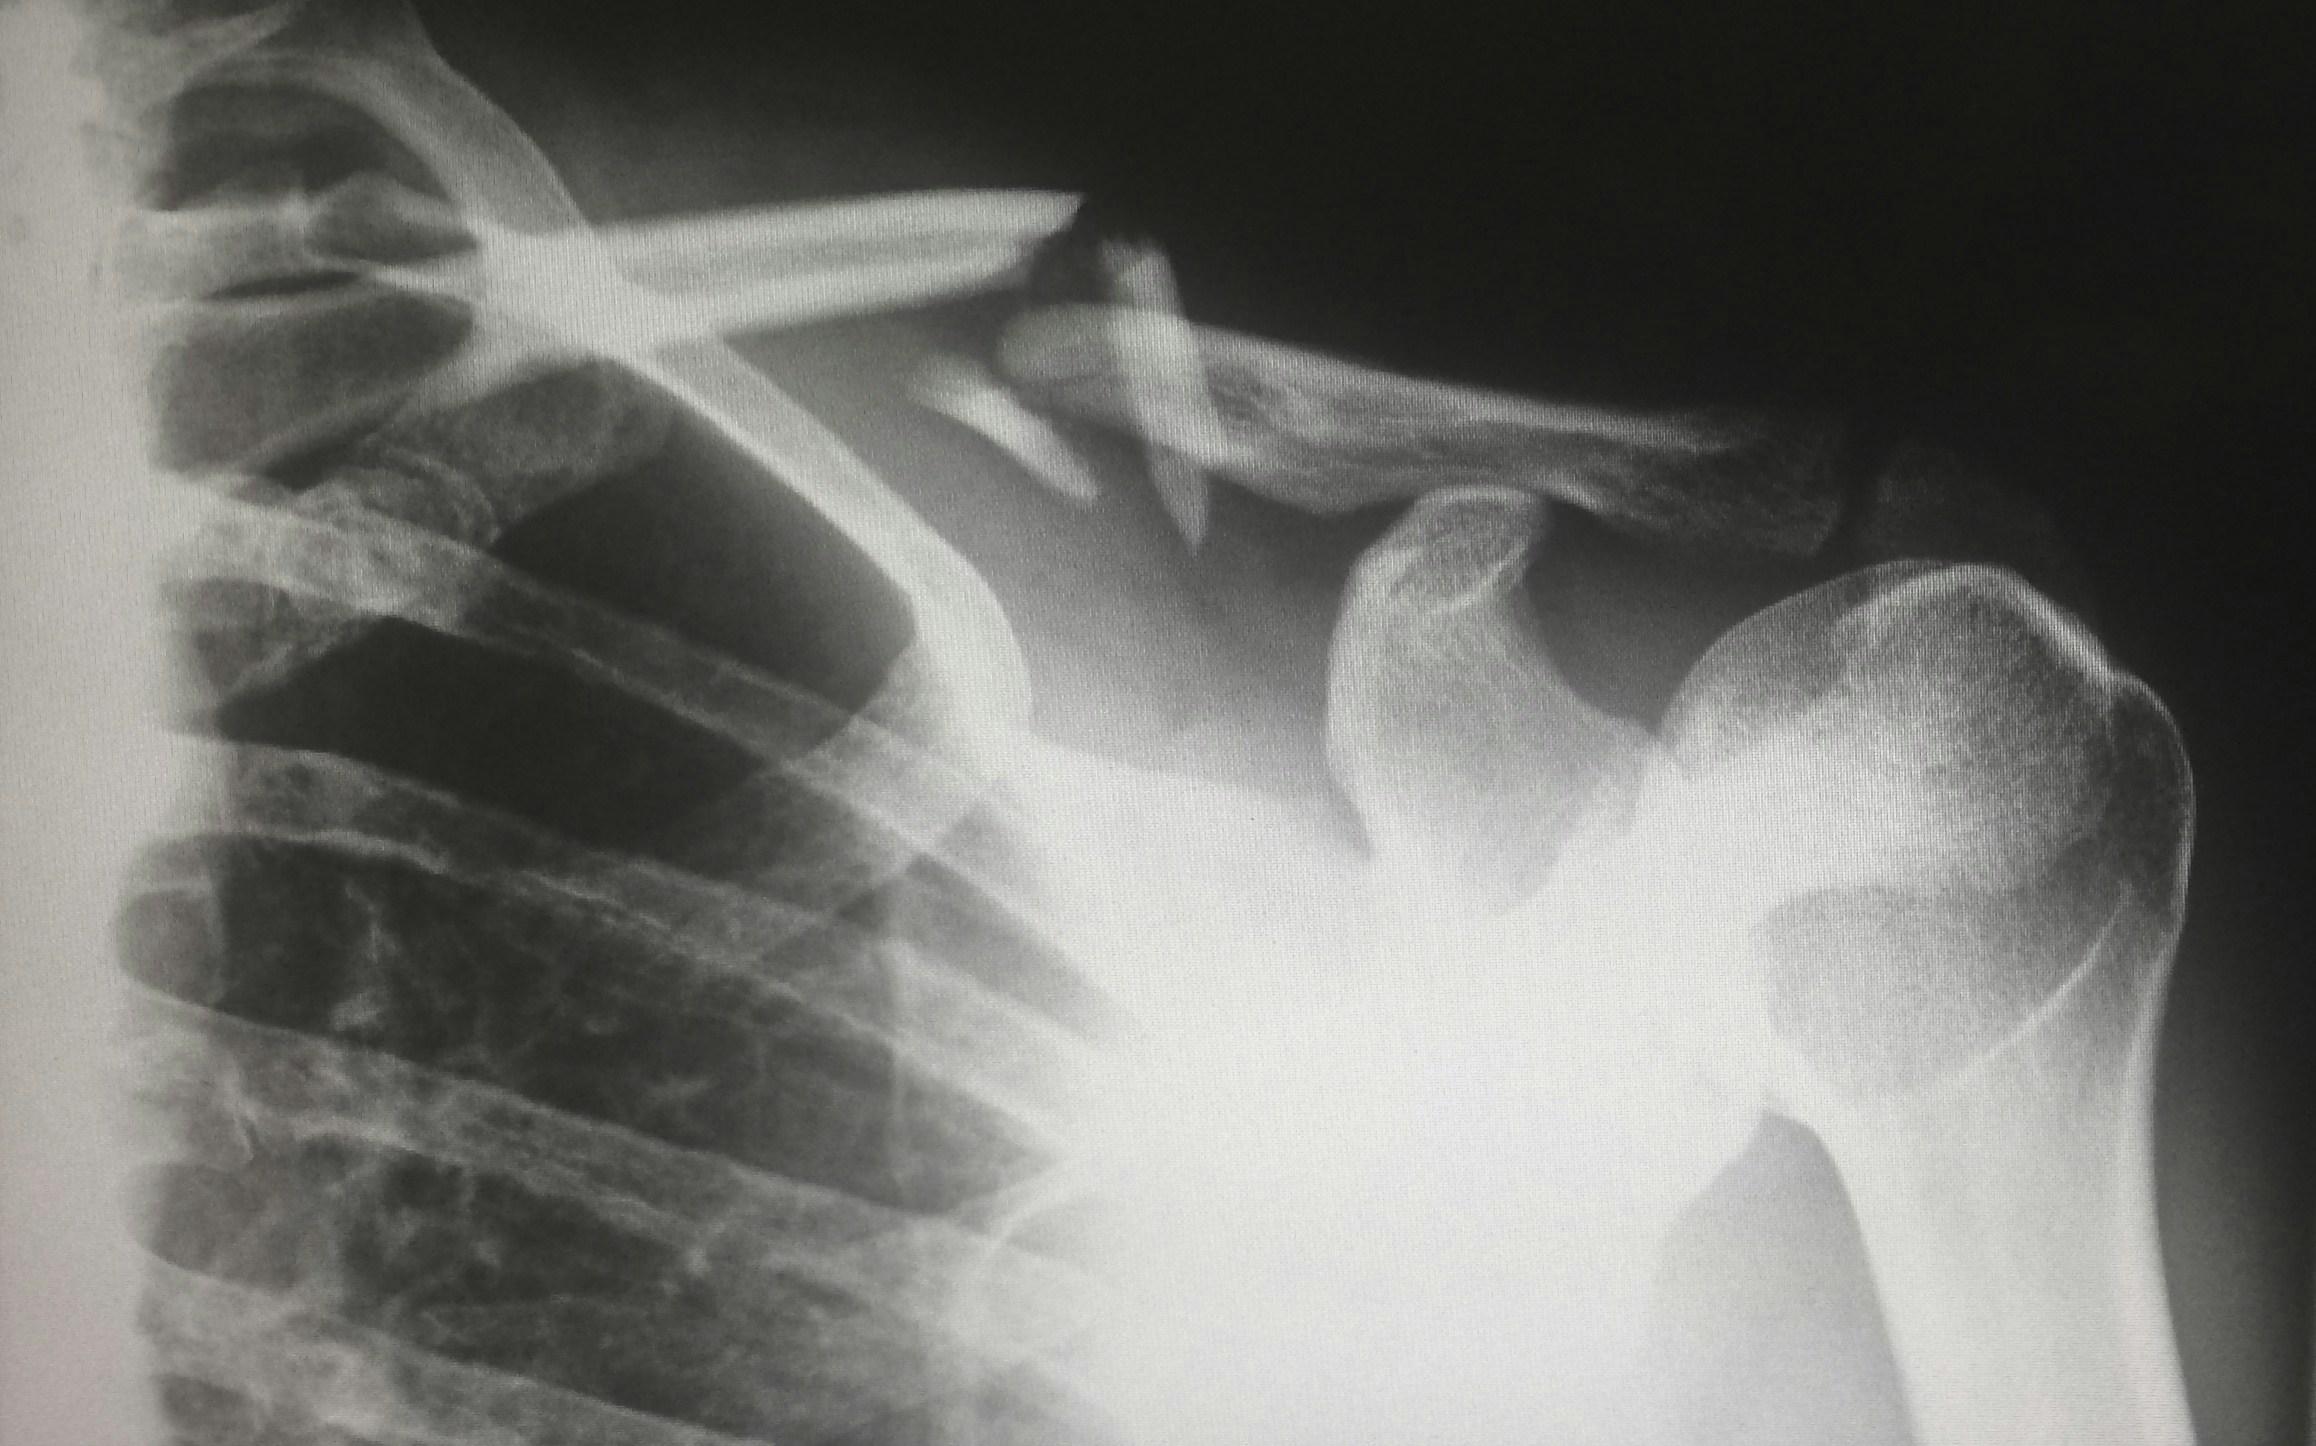

Warum kann Knochen narbenlos heilen, während andere Gewebe kaum regenerieren? 🦴✨

) / @npub16gph...7pmq ) über „gezielte zelluläre Selbstorganisation zur Förderung der Knochenregeneration“ und gibt spannende Einblicke in den SFB1444.

„Gezielte zelluläre Selbstorganisation zur Förderung der Knochenregeneration“